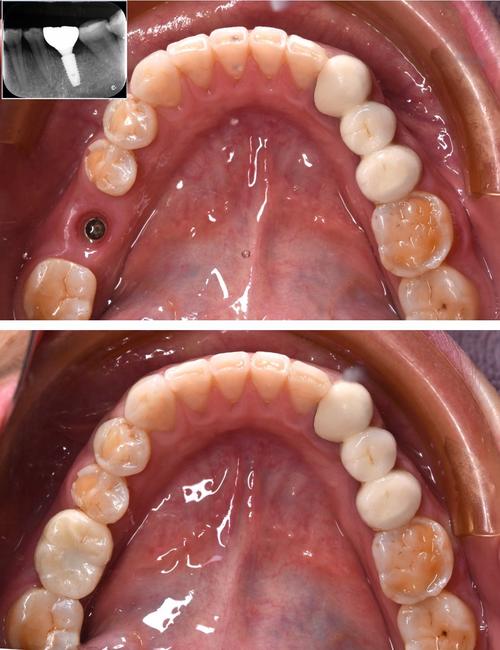

(图片来源网络,侵删)- 临床检查: 视诊(观察牙龈颜色、形态、肿胀、出血情况)、探诊(检查牙龈是否有出血、牙周袋深度)、叩诊(检查牙齿是否有敏感或疼痛)、扪诊(检查是否有压痛或波动感)。

- 咬合检查: 用咬合纸或 Articulating 纸检查牙冠的咬合接触点,看是否有早接触或干扰。

- X光检查: 拍摄根尖片或全景片,评估牙冠边缘的位置、与牙龈的关系、种植体周围骨组织的情况(排除种植体周围炎)。

- 取模或扫描: 如果怀疑牙冠边缘或形态问题,可能需要重新取模或扫描。